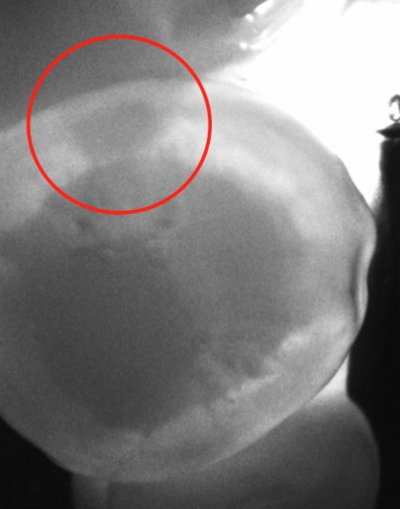

widok z kamery diagnocam - pomoc w diagnozie

DIAGNOcam to zaawansowane narzędzie diagnostyczne, które wykorzystuje technologię światła wizyjnego do skanowania i analizy struktury zębów. Jest to niezwykle precyzyjne urządzenie, które umożliwia wykrycie nawet najmniejszych zmian w strukturze zębów, włączając w to początkowe stadium próchnicy, nadżerki czy inne patologie.

Działanie DIAGNOcam opiera się na zasadzie skanowania powierzchni zębów za pomocą promieniowania świetlnego. Specjalny sensor analizuje odbicia światła, identyfikując obszary, w których występują zmiany w strukturze zębów. Dzięki temu, lekarze stomatolodzy w SmileUp mogą szybko i skutecznie zidentyfikować wszelkie patologie, nawet te niewidoczne gołym okiem.